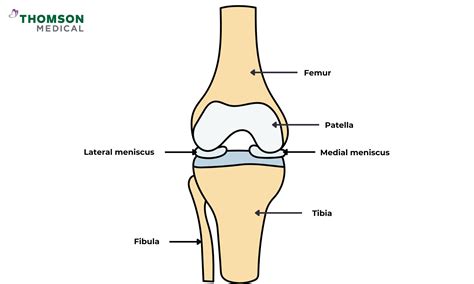

The meniscus is a C-shaped piece of tough, rubbery cartilage that acts as a shock absorber between your shinbone (tibia) and your thighbone (femur). You have two menisci in each knee joint, and they play a critical role in distributing weight and stabilizing the knee. A meniscus tear often occurs due to sudden twisting or rotating of the knee, especially when the foot is planted firmly on the ground while the rest of the leg is in motion. Common symptoms include a popping sensation at the time of injury, pain, swelling, and a feeling that the knee is "locking" or giving way.